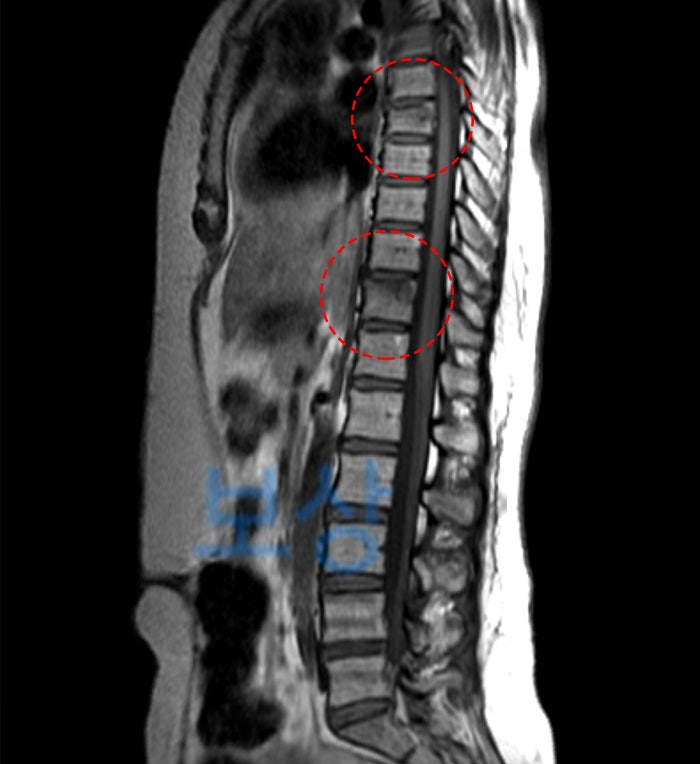

이 사고로 환자분은 등 쪽의 척추뼈인 흉추 7번, 11번(T7, T11) 골절되었는데요. 위 MRI 영상을 보면 약간 변색되어 찌그러진 척추체를 확인하실 수 있습니다. MRI 검사에서 뼈의 색이 어둡게 나타나는 것은 급성 골절이라는 의미인데요. 오래된 골절(진구성 골절)은 뼈의 색깔이 동일한 흰색으로 보입니다.

또한 척추체 골절인 경우, 부러지는 형태가 아니라 찌그러지는 형태로 나타납니다. 그래서 흔히 **'압박골절'**이라는 표현을 사용합니다.

제7흉추 압박률 30% 제6흉추 - 제8흉추 간 후만각 21도

척추에 뚜렷한 기형을 남긴 때(30%)